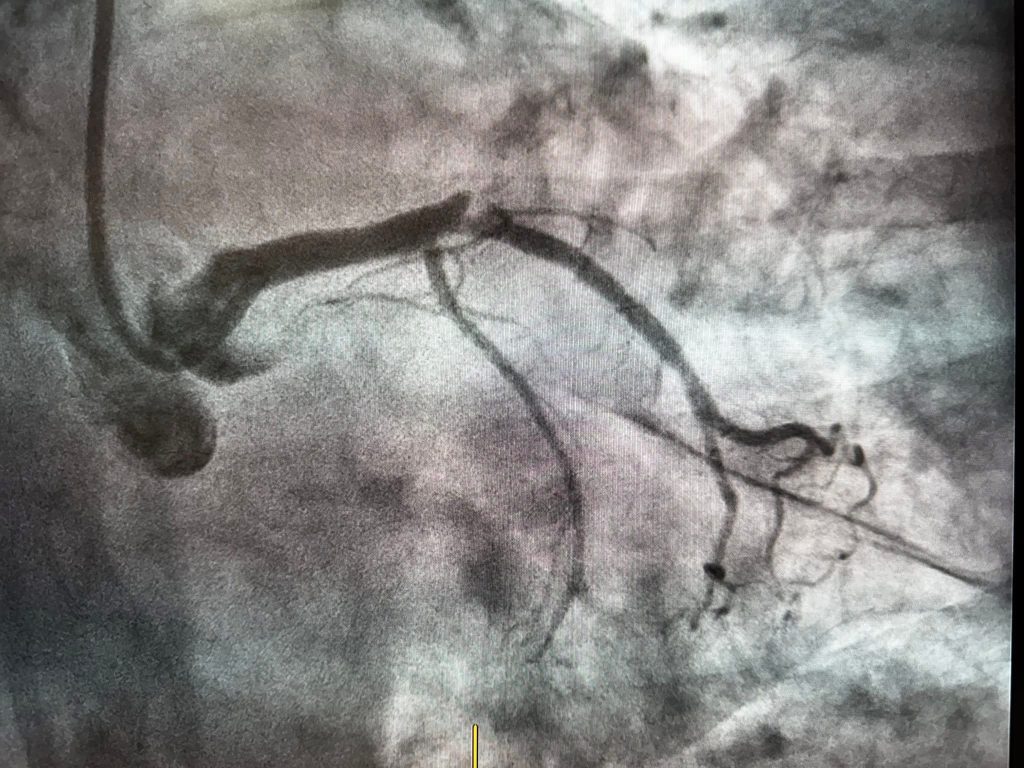

Intervenția a constat în implantarea unui stent și dezobstrucția completă a vasului afectat, procedura fiind realizată cu succes, fără complicații.